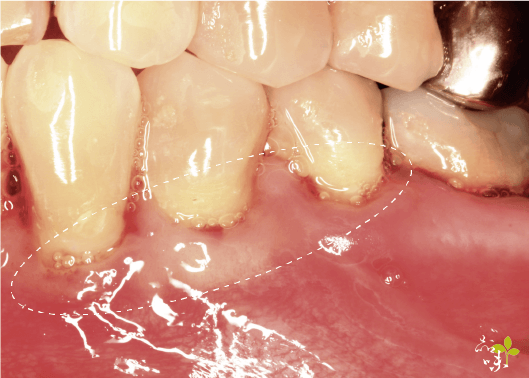

治療時,醫生會用特殊的針,在患部牙齦上刺一個小洞,接著使用專利的器械,透過這個針孔從內部翻瓣,再填入再生膜。一般來說,可以恢復原有牙齦高度的 80-90%。

通常做完的病人牙齒敏感的狀況會改善很多,美觀上有改善,牙齒不會看起來這麼長。